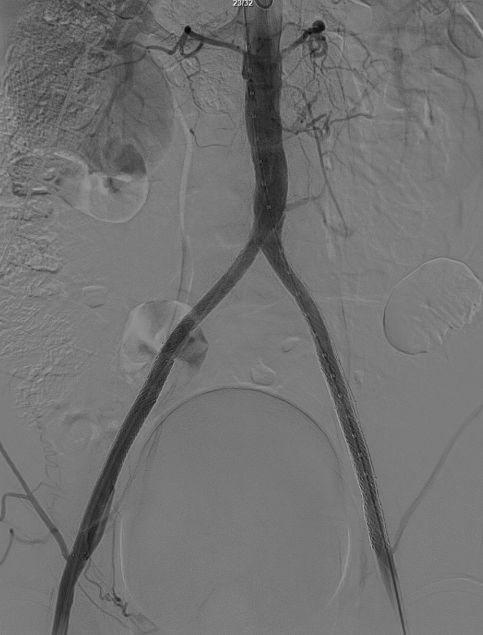

即时效果:造影显示腹主动脉、双侧髂总/髂外动脉及股动脉通畅。

术后对患者应用利伐沙班进行抗凝治疗,同时给予阿司匹林抗血小板治疗,期望右侧股动脉闭塞病变能通过自身纤溶作用实现再通。

3个月复查:右侧股动脉完全再通,无残存狭窄;CTA显示腹主动脉、双侧髂动脉及远端股动脉通畅,双侧ABI>1.0;左侧髂动脉开口打开不全(推测与对吻球囊直径选择有关,原用8mm,若选10mm可能避免),因患者无症状,暂密切随访,远期若再狭窄可采用10mm球囊扩张。